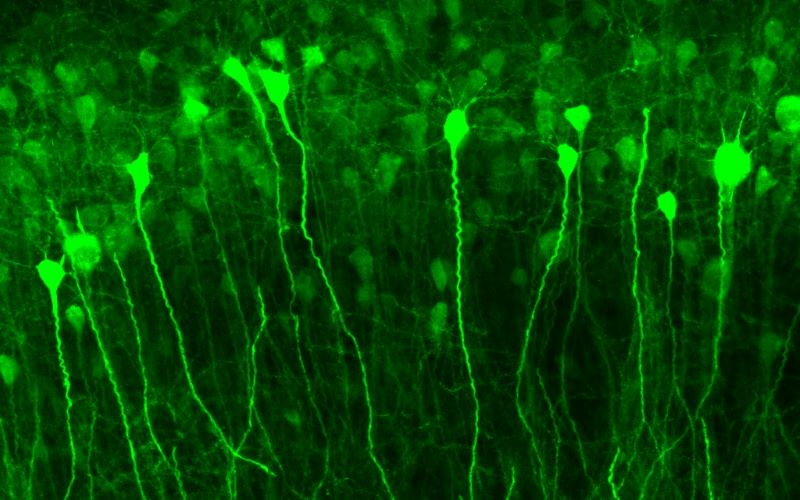

Experimental Epilepsy Group @ Institute of Neurology, UCL. Neuronal and Synaptic physiology, Super Resolution, Optogenetics and Gene Therapy.